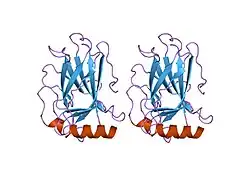

Diagnostic and prognostic significance

This image shows different patterns of p53 expression in endometrial cancers on chromogenic immunohistochemistry, whereof all except wild-type are variably termed abnormal/aberrant/mutation-type and are strongly predictive of an underlying TP53 mutation:[92]